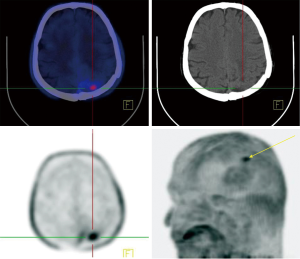

PSMA is a type II transmembrane glycoprotein which is overexpressed in prostate cancer and its expression levels are positively associated with tumor grade and stage (53). Also, PSMA expression is increased with conditions like hormone resistance, metastatic lesions, and anaplastic properties in tumor (54). Although PSMA was found in prostate glands for the first time but further histologic studies revealed it could be found in other healthy tissue as well, including salivary glands, lacrimal glands, duodenal epithelium, proximal tube cell of the kidney (55,56). Of note, it has been detected in in healthy tissues (as mentioned earlier), benign conditions (e.g., meningiomas in the brain), and malignant tumors both prostatic-originated and non-prostatic-originated tumors, therefore questioning the sensitivity and specificity of PSMA as a specific prostatic tracer (53,57,58). Since the development of 68Ga-labeled PSMA, a PSMA-targeted small molecule labeled with 68Ga, investigators are equipped not only to visualize the prostate cancer throughout the human body, but also to use it as a therapeutic target (59-61). Although PSMA has been developed to assess the management of prostate cancer, the expression of PSMA has been seen in different nonprostatic malignant and nonmalignant conditions causing to probable difficulties in the analysis of PSMA-targeted studies. On the other hand, this limitation may indicate favorable in imaging and therapeutic agent for other nonprostatic conditions (53,56). 68Ga labeled PSMA is increasingly incorporated in the routine clinical assessment of patients affected by prostate cancer. Whole-body 68Ga-PSMA scan can be useful in the initial staging of intermediate or high risk prostate cancers and in restaging after biochemical clue of tumor recurrence (62,63) (Figure 7).

Healthy brain tissue does not show any PSMA uptake which makes it a promising tracer in detecting metastasis of prostatic cancer to the brain, but studies reported new connections between PSMA uptake and nervous system tumors other than prostatic metastasis (57,59). Up to present, several studies have reported PSMA expression in few nervous system tumors (53) including meningiomas, schwannomas, peripheral nerve sheath tumors as well as other benign conditions such as sympathetic chain ganglia (58,64-71). So far, two prostatic cancer patients are reported who showed incidental increased uptake of 68Ga-PSMA-11 (PET/CT) with corresponding MRI imaging consistent with meningiomas (58,64). PSMA-radiotracer uptake in other neurogenic conditions occurs in scenarios similar to meningiomas. Regarding the low incidence of prostatic cancer metastasis to the brain and lack of tracer uptake by the healthy brain, it seems reasonable to consider further imaging or even examining tissue biopsies to confirm the diagnosis. These recent studies gave us better insights into the PSMA expressions status throughout the body and, with this in mind, increased uptake of PSMA-targeted tracers in the brain of prostatic cancer subjects may require further imaging to establish the diagnosis.